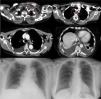

Cortes axiales de TAC que muestran colección laterocervical-supraclavicular izquierda extendida difusamente por todos los compartimentos mediastínicos (marcadas por elipse), con derrame pleural bilateral. A) Radiografía PA de tórax tras retirada del drenaje pleural izquierdo, manteniendo el drenaje pleural derecho. B) Radiografía PA de tórax realizada como control de seguimiento 3 meses después del episodio, apreciándose resolución completa del derrame pleural bilateral.

Presentamos el caso de una paciente de 60 años, con antecedentes de hipertensión arterial, dislipidemia e hipotiroidismo tratado farmacológicamente. Tras un estornudo intenso presentó tumefacción supraclavicular izquierda, acompañada de mareo, por lo que acudió a Urgencias. En la radiografía de tórax se observó derrame pleural basal bilateral; tras efectuarse una TAC cérvico-torácica se apreció colección laterocervical-supraclavicular izquierda que se extendía por todos los compartimentos mediastínicos, con derrame pleural bilateral (fig. 1), interpretado radiológicamente como hematoma tras estornudo violento. Se mantuvo actitud expectante y, tras evidenciar progresión radiológica bilateral del derrame, se colocaron sendos drenajes endopleurales. En ambos hemitórax se obtuvo un líquido de aspecto quiloso, cuyo estudio analítico bilateral confirmó que se trataba de un exudado estéril rico en triglicéridos (2.241mg/dl en el hemitórax derecho y 2.160mg/dl en el izquierdo). Tras confirmación diagnóstica de quilotórax bilateral, se instauró tratamiento dietético con restricción de grasas. El débito por ambos drenajes cedió progresivamente, manteniendo un aspecto seroso tras iniciar la restricción dietética y confirmándose la resolución bioquímica del quilotórax. Dada la evolución favorable, se omitió instaurar otras medidas terapéuticas, pudiendo retirarse el drenaje pleural izquierdo a las 48 h (fig. 1 A) y el derecho a los 5 días. Tras retirada de los drenajes, el control radiológico confirmó la resolución bilateral del derrame. Durante el seguimiento en Consultas Externas, se evidenció la resolución clínico-radiológica del cuadro (fig. 1 B).